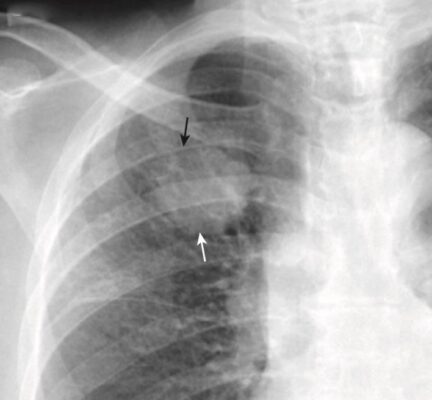

- Bệnh khoang chứa khí có thể biểu hiện dấu bóng bờ (dấu xoá bờ – silhouette sign) (Hình 4).

- Dấu xoá bờ xảy ra khi hai cấu trúc có cùng mật độ X quang (chẳng hạn như nước và mô mềm) chạm vào nhau sao cho rìa hoặc bờ giữa chúng biến mất. Không thể nói cấu trúc này này bắt đầu ở đâu và cấu trúc kia kết thúc ở đâu. Dấu hiệu bóng bờ không chỉ có giá trị ở ngực mà còn hỗ trợ cho việc phân tích các nghiên cứu hình ảnh ở những vị trí khác.